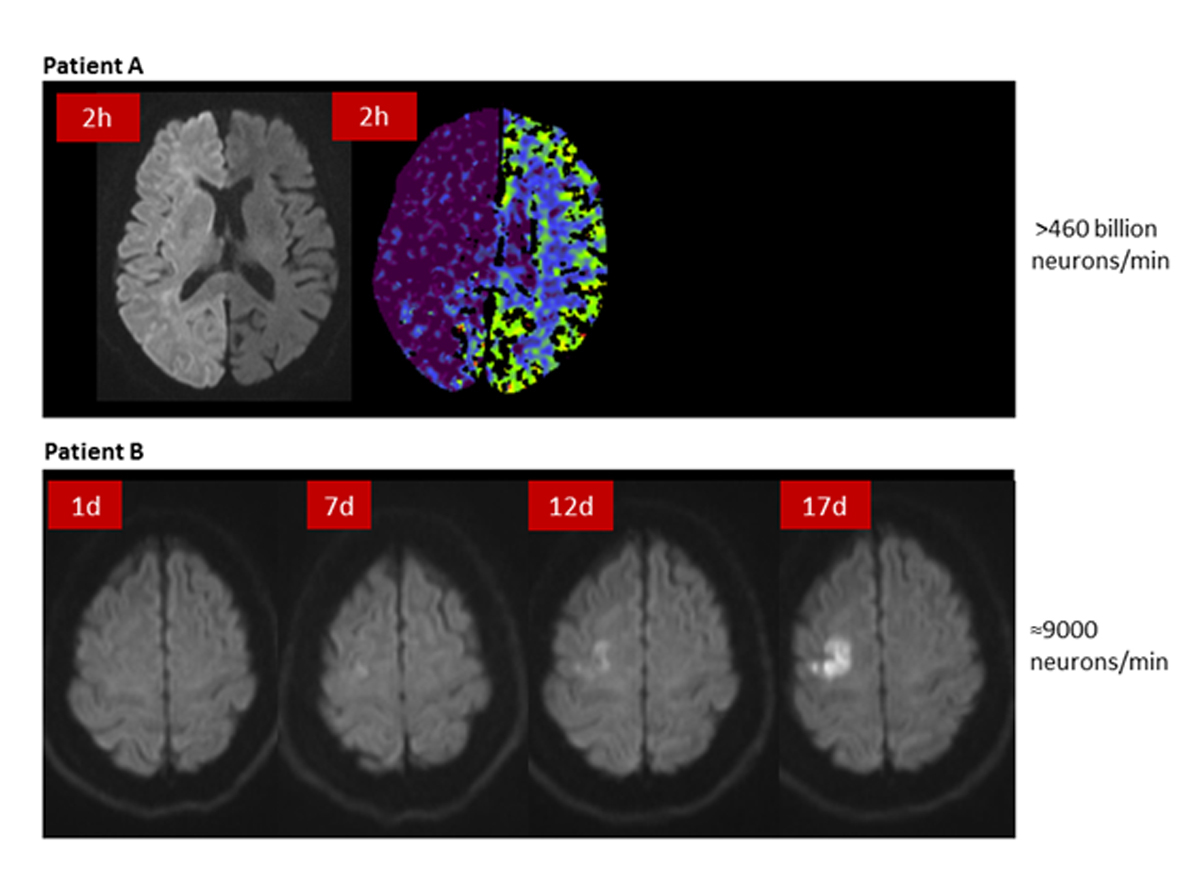

Reperfusion therapy by means of IVT and EVT is highly effective. In large randomised trials only 5–14 patients had to be treated with IVT and 3–7 patients with EVT to prevent one patient from death or dependency [2–10]. The therapeutic effect of these therapies is not only dependent on the success of reperfusion, but is also highly time dependent. Treatment time windows of 4.5 hours for IVT and 7.3 hours for EVT have been defined by pooled analysis of the patients treated in the large trials [43, 44]. Although patients on average may not benefit from later therapy, patient selection based on these time windows would neglect the large interindividual variability of the extent of collateral flow. This regimen would lead to the exclusion from therapy of many patients who would, in fact, benefit. Indeed, infarct growth is much less dependent on the elapsed time than on the quality of collaterals: good collaterals slow down infarct growth and poor collaterals accelerate it [19, 45–48]. Of course reperfusion treatment should always be initiated as early as possible because “time is brain”, but the collaterals set the pace of neuronal loss, and with this the individual time window until infarction of all tissue at risk. Figure 4 illustrates two patients in whom the approximated velocity of neuronal cell loss differed between 9000 neurones/min and more than 460 billion neurones/min. This large variability of the velocity of neuronal cell loss implies that there are probably many patients eligible for therapy far beyond time windows that were calculated on the average of patients. Patient selection based on restricted time windows would not only exclude from therapy eligible patients outside the time windows, but also all patients with wake-up stroke and with unknown symptom onset, who account for at least one third of all stroke patients. Therefore, patient selection for reperfusion therapy should be individualised by imaging salvageable tissue, rather than being restricted by strict time windows.

Figure 4 Variable velocities of infarct growth. Patient A: carotid T occlusion and fetal type posterior cerebral artery, 2 hours after symptom onset hyperintensity of the whole hemisphere in diffusion-weighted imaging (DWI) with corresponding hypodensity in CT perfusion (CBV). Patient B: persistent carotid occlusion, slow infarct growth in DWI over 17 days. Neuronal cell loss was estimated based on volumetric measurement of the lesion and the average neuronal density described in Saver et al. [13] (Pictures: Stroke Centre Bern)